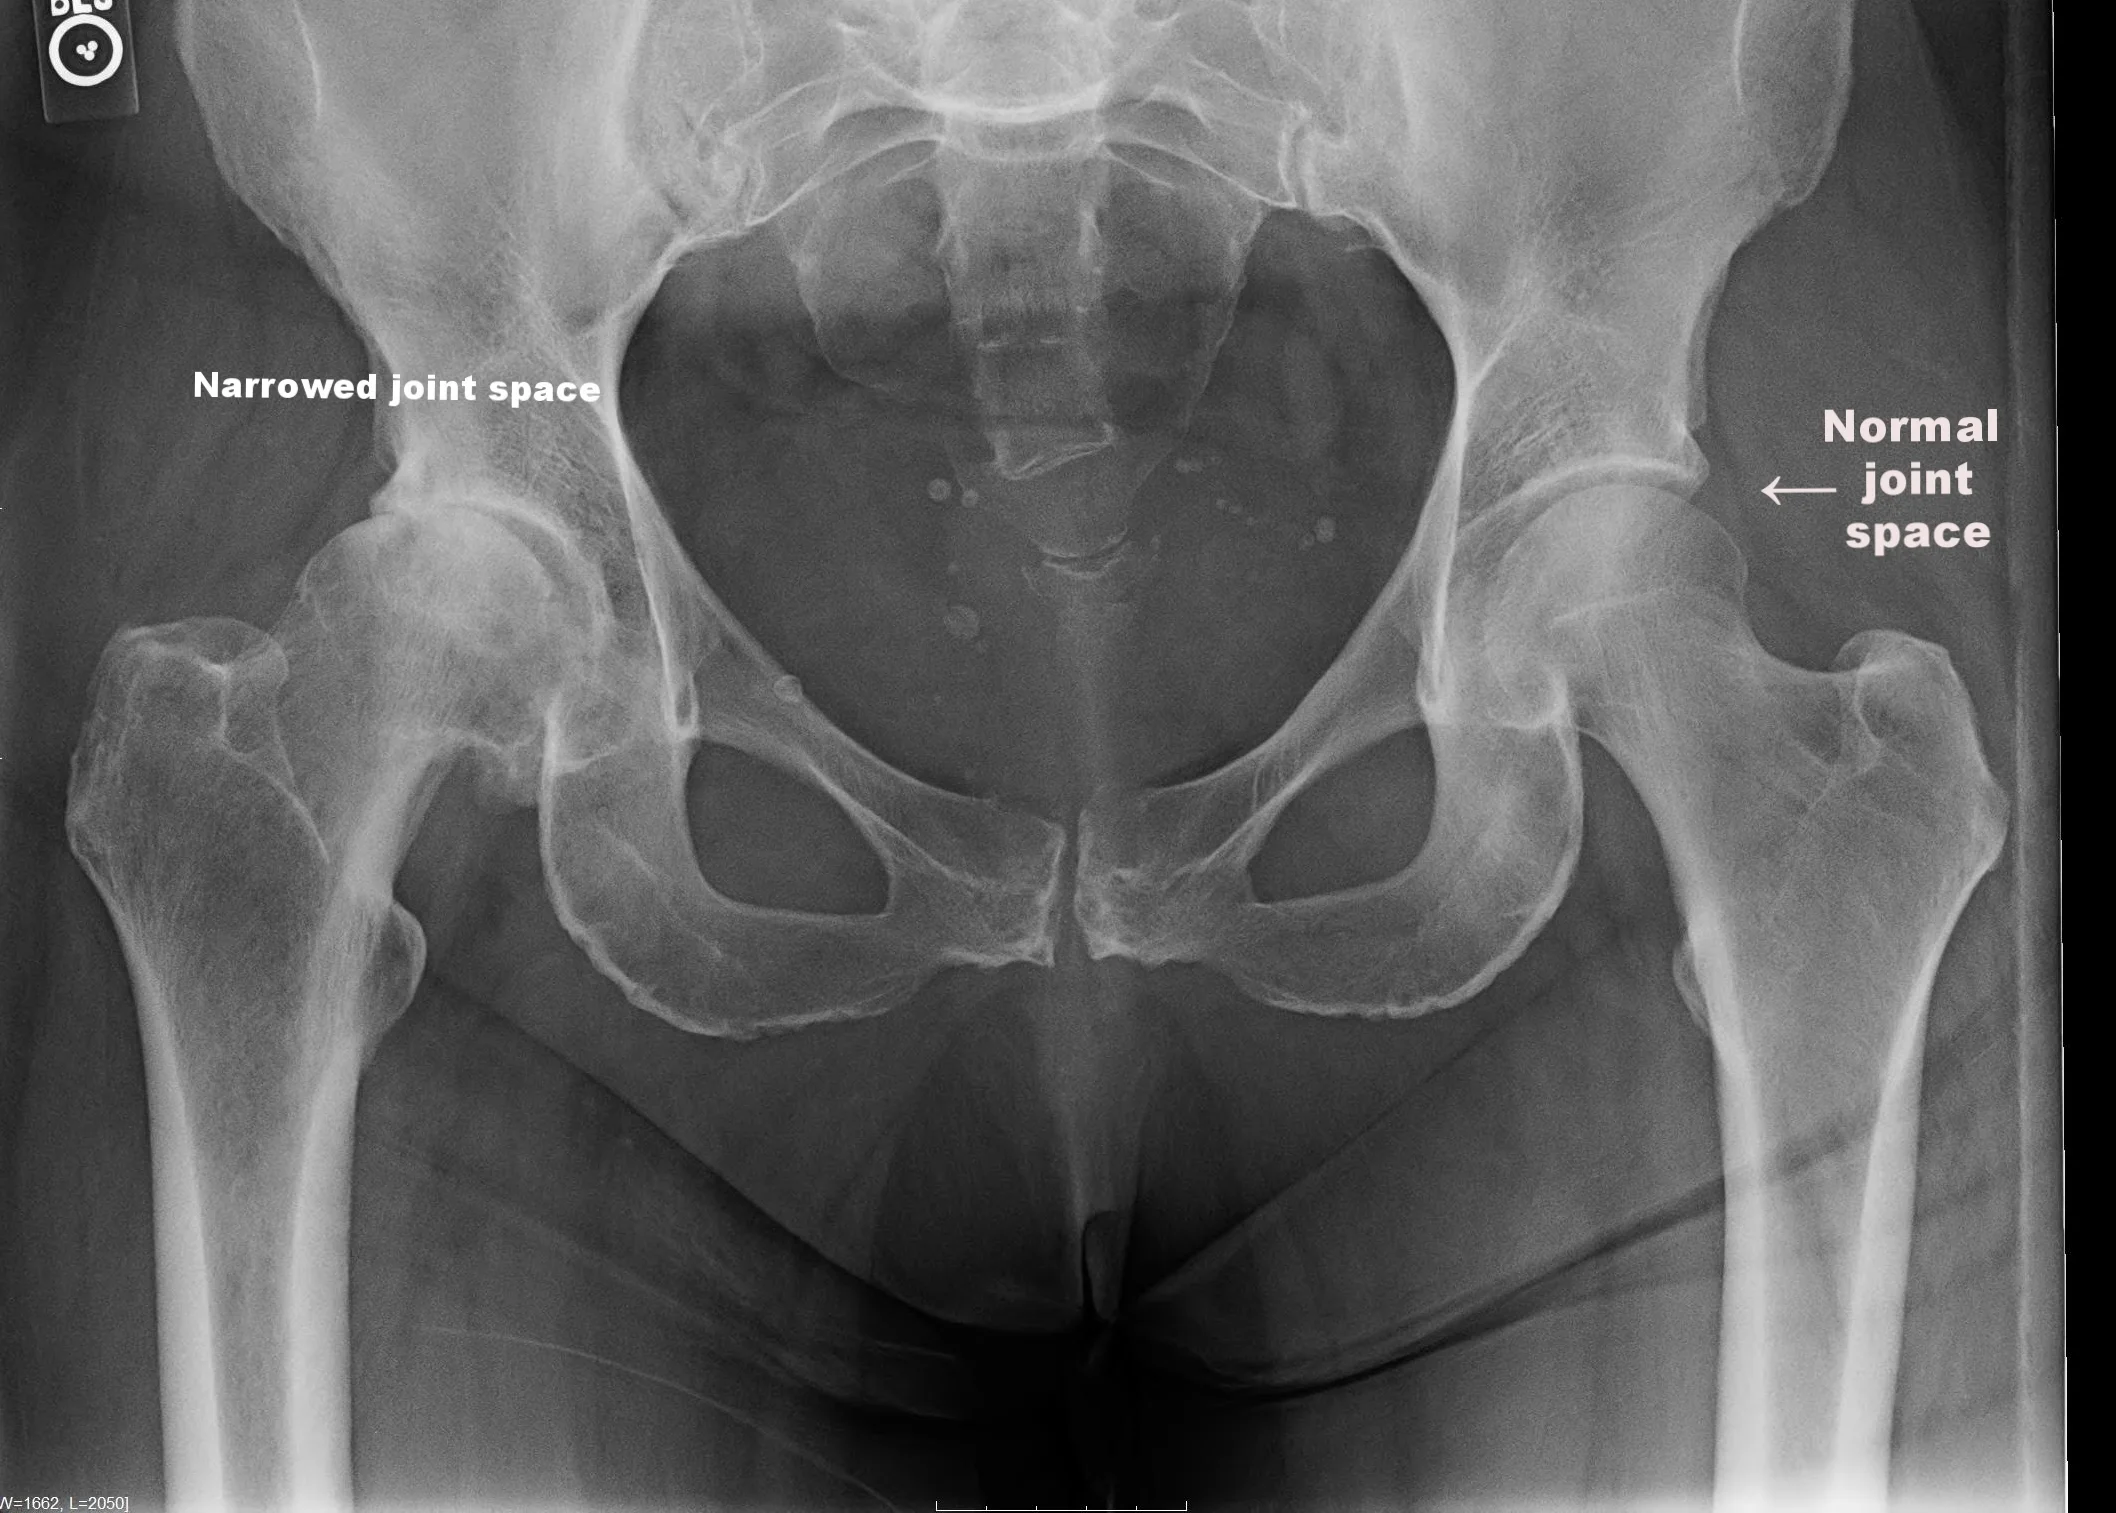

Osteoarthritis also referred to as Degenerative Joint Disease is defined as inflammation of a joint associated with loss of articular cartilage the shiny tissue on the end of the bone within a joint.

Degenerative joint disease DJD or osteoarthritis is a nonsystemic noninflammatory progressive disorder of movable joints that is associated with aging and accumulated trauma. The clinical and radiographic findings may be subtle. Degenerative joint disease occurs when the cartilage cushioning the bones breaks down and the bone surfaces become exposed and rub together.